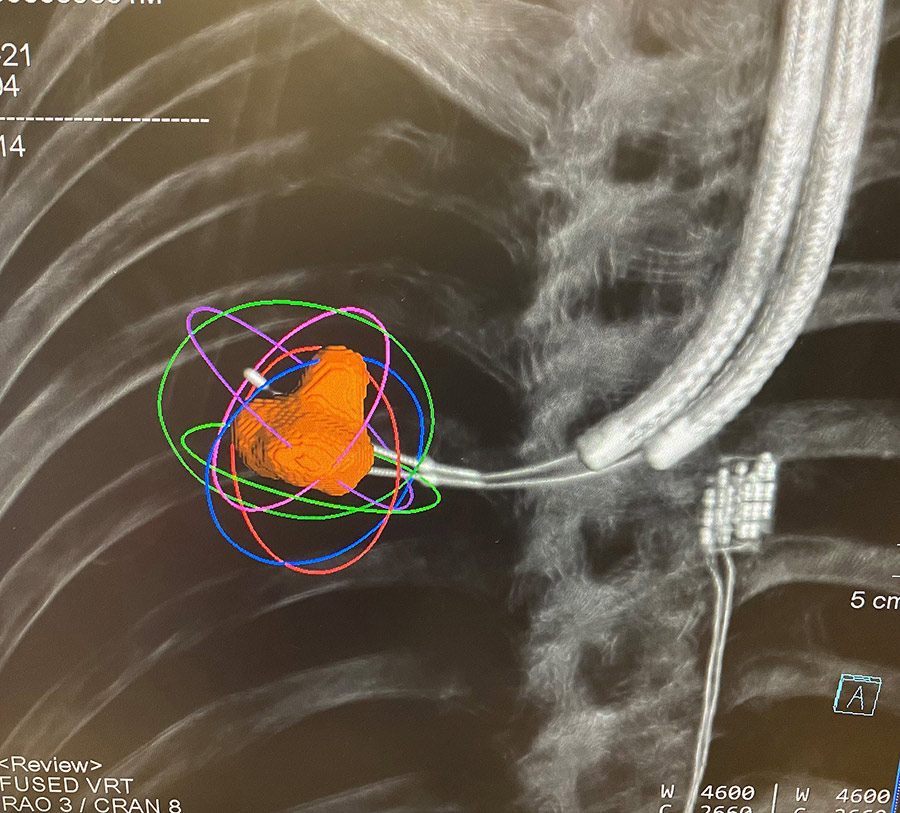

BMA混合操作室使用前沿CT扫描成像设备电磁导航支气管检查是一种先进支气管检查形式并配有GPS特征,外科医生精确定位天线切入肺癌并使用生成的微波能热消除恶性组织高风险外科病人或拒绝外科和放射理疗者可受益于这种独特的肺癌治疗

Calvin Ng博士Thoracic外科团队已成为世界最富经验团队 非入侵支气管反射波演播室中肺癌理疗混合操作室成功应用并展示这一技术治疗肺癌2019年3月,他们执行亚洲-太平洋区域第一个BMA案例团队截至2021年6月28日已成功完成74个BMA案例过程期间没有失血,超过80%的病人报告没有程序后疼痛多数BMA烧伤病人次日出院,大大快于常规最小入侵外科手术,该手术需要3至5天住院时间。

多肺异位发现 患者有肝细胞癌历史BMA外科剖分解合并成混合战区单次操作解析有了适当的边缘癌症实现,所有肺部转移都成功处理混合战区BMA电磁导航为多项肺肿瘤运算法提供新帮助面向多路分点相容并关注肺功能的个人的一式处理选择

Calvin Ng博士及其团队共从25名病人中处理30个肺膜检测到100%技术成功率,某些结核需要同系双重烧损当前发现鼓励并证明研究应用BMA技术治疗肺癌有理反溯性调查证明支气管跨支气管微波烧损处理肺结核的安全和可行性还必须研究影响熔化区大小的关键因素,如肺延缩测量和水分测量本地控制率和生存率等长期结果对监控也很重要。跨支气流肺癌消退很可能成为个人化癌症治疗令人振奋的时代的重要资源,同时与语道内化疗或其他形式的跨支气流内分解术并发